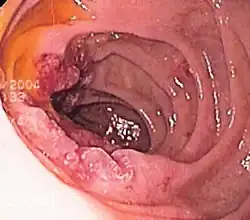

_carcinoid.jpg) Carcinoid

Carcinoid